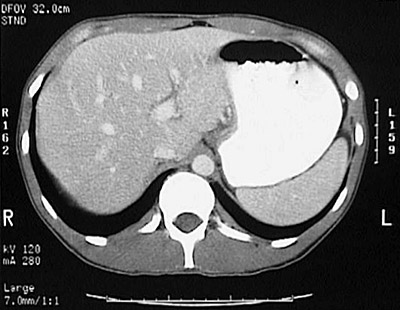

| CT scan of a cirrhotic liver. Again, the difference in the tissues is noticeable. |